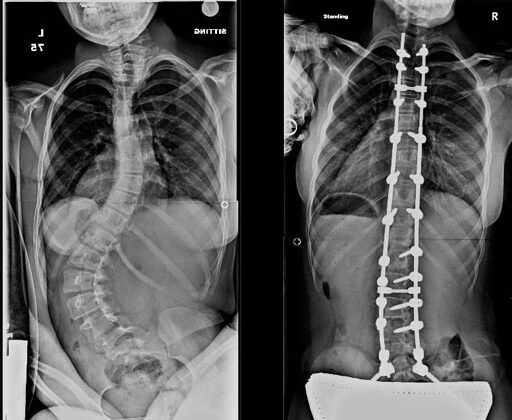

جراحة تثبيت العمود الفقري هي عملية تهدف إلى تقويم الانحناء وتثبيت الفقرات في وضع أكثر استقامة.

- تعديل شكل العمود الفقري

- تثبيت الفقرات باستخدام شرائح ومسامير

- منع زيادة الاعوجاج مع الوقت

الهدف الأساسي ليس فقط تحسين الشكل الخارجي، بل أيضًا تحسين وظائف الجسم اليومية، مثل الجلوس والراحة.